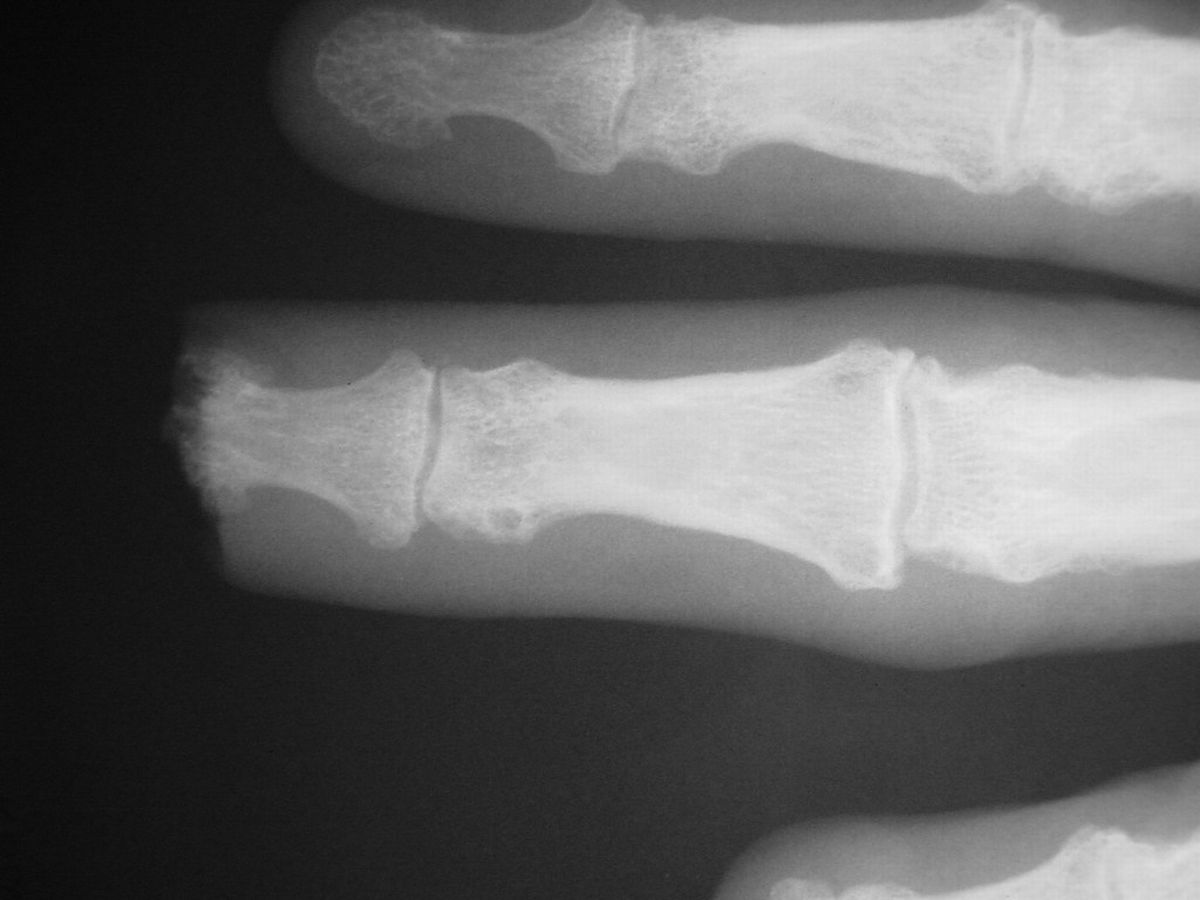

| Case

4. A dog bit off this young man's index fingertip. Although the PA Xray looks as though the bone was kept, additional views show an amputation through the tuft. |

| The defect. |